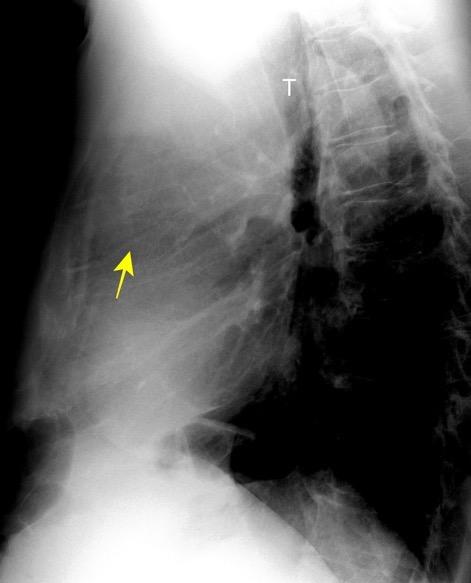

Raro. (2-9% de los T. tímicos). Asintomático. Contiene grasa (hasta 90%) y tejido timico (10-33%). Pueden ser muy grandes y confundirse con cardiomegalia. La tomografía “clásica” muestra los límites de la silueta cardiaca. (flechas)

Líneas paraespinales formando un “paréntesis” por encima del diafragma. El signo señala el origen “intratorácico” de la lesión.